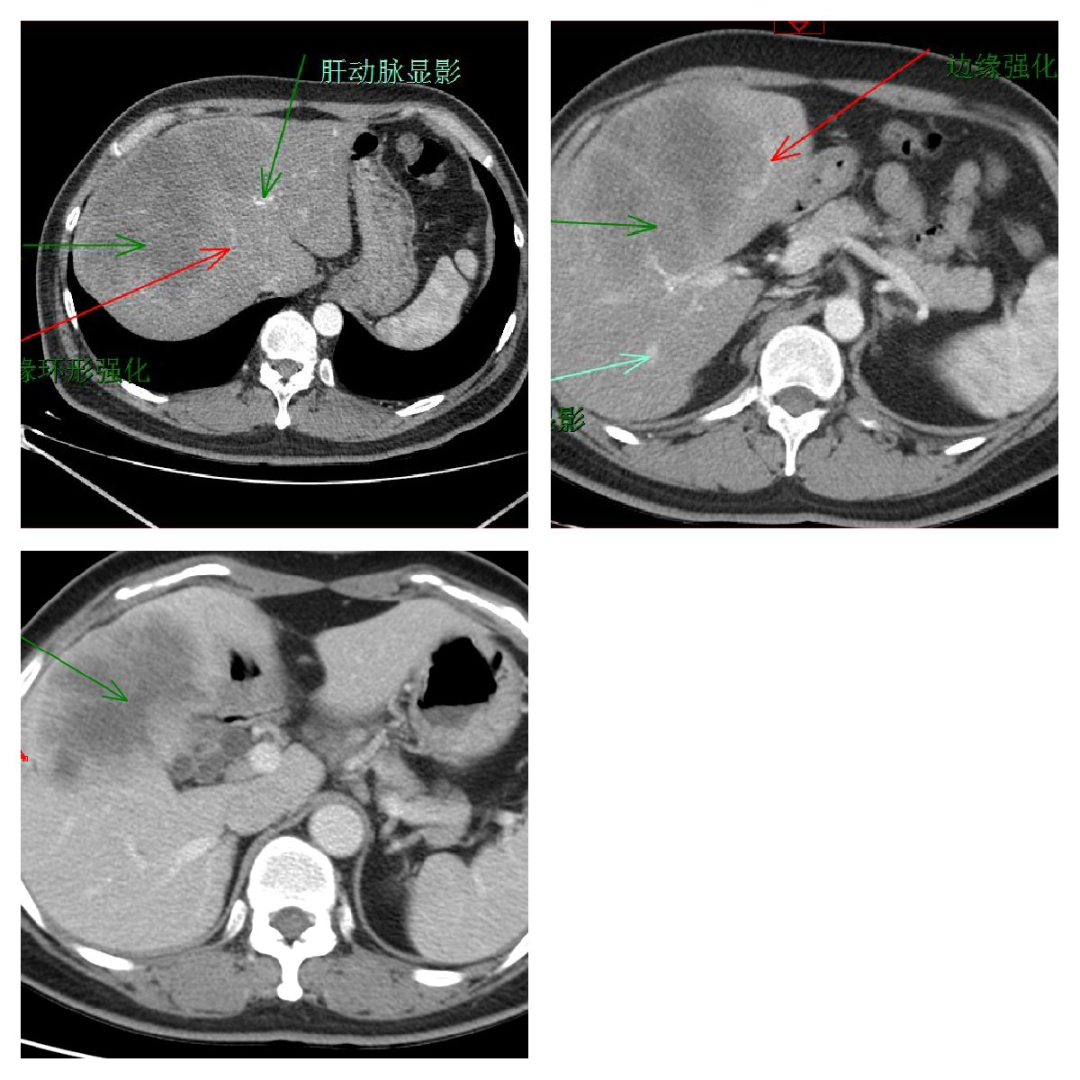

肝内胆管细胞癌:动脉期不规则环形强化,边界不清;静脉期及延迟期造影剂缓慢向肿瘤中心渐入的「延迟强化」。

结肠癌肝转移:肝转移瘤一般在动脉期多发,呈「牛眼征」样强化,静脉期及延迟期继续为环形强化;通常与肝内胆管癌需要用 pet-ct、胃肠镜做鉴别诊断。

肝脓肿:CT 动脉期环形强化,静脉及延迟期界限不清,伴发热,消炎后好转。